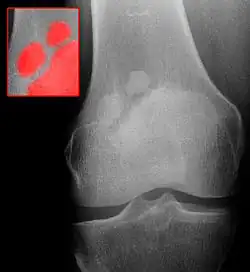

Die Patella partita (lateinisch patella = Schüssel, Teller; partiri = teilen) ist eine Störung der Ossifikation der Kniescheibe ohne eigentlichen Krankheitswert.

Die Kniescheibe ist zunächst knorpelig angelegt und bildet sich aus mehreren Knochenkernen (Ossifikation), die im Laufe des Wachstums verschmelzen. Bleibt diese aus, entsteht eine im Röntgenbild sichtbare scheinbare Teilung der Kniescheibe in zwei (Patella bipartita), drei (Patella tripartita) oder mehrere (Patella multipartita) Anteile. Die umgebende knorpelige Anlage ist nicht geteilt.

Typischerweise tritt die Veränderung einseitig und am oberen äußeren Patellaanteil auf.

Die Diagnose wird im Röntgenbild gestellt. Die unverbundenen Anteile finden sich meist im oberen/seitlichen Rand der Kniescheibe.